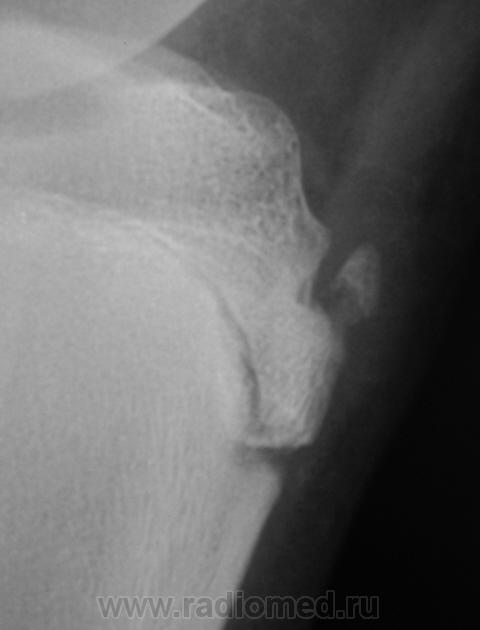

Пациент направлен на рентгенографию коленного сустава с диагнозом - Болезнь Осгут - Шлаттера.

фрагментация бугристости Б\Б кости

Болезнь Осгут - Шлаттера, как-то не вдохновляет. Более склонен к консоидирующемуся отрывному перелому бугристости б/берцовой кости.

Более склонен к варианту окостенения, хотя травматический генез, как и асептический некроз (абсолютно согласен с Максималистом - при наличии клиники и анамнеза) с повестки дня окончательно, до выяснения оных, не снимаются.

Уважаемые коллеги! На мой взгляд, выявленное на рентгенограмме, образование костной плотности, с четкими, ровными контурами, однородное по своей структуре отношения с бугристости большеберцовой кости не имеет. Хотелось бы знать возраст пациента, его анамнез (спорт, травмы области коленного сустава). Больше похоже на обызвествления собственной связки надколенника. Дополнил бы УЗИ коленного сустава.

16 лет "учтенному лицу", ранее жалоб не было, рядом "мама", которой доктора посоветовали..., вот и вся история...